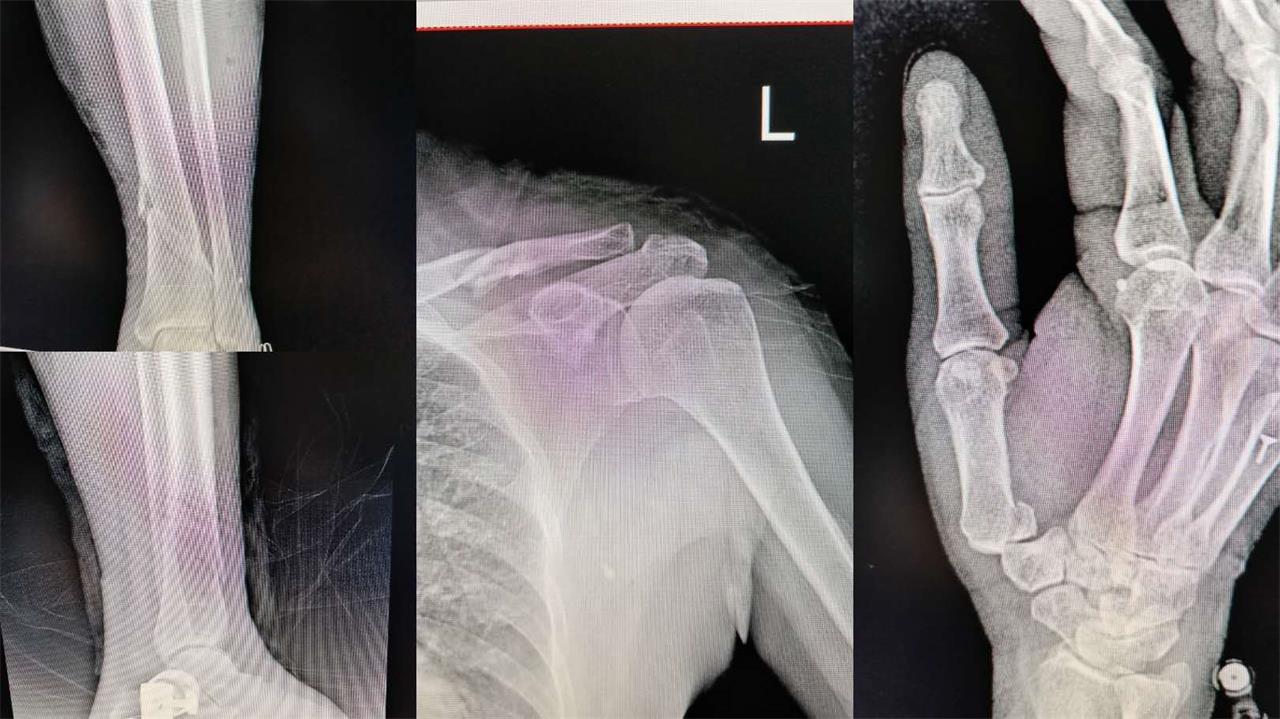

今年的张阿婆已有80岁高龄,早在2017年,张阿婆在驾驶电瓶车时,操作不当,导致侧翻,沉重的电瓶车压在张阿婆的腿上,造成全身多处骨折,其中左胫骨开放性粉碎性骨折,在当地医院简单处理了伤口,特地转至台州市博爱医院,请郭医师亲自为她做手术。

其实,这不是郭医师第一次给张阿婆做手术了,早在2015年前,张阿婆右髋关节骨折,来医院置换人工髋关节,正是郭医师做的手术。